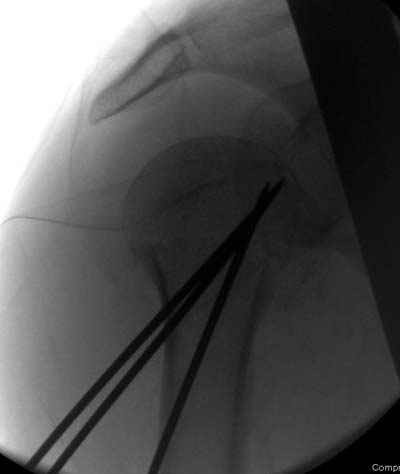

Клинические снимки - 3 недели после операции

Посылаю послеоперационные Рг граммы.

Поздравляю, получилось просто замечательно. Если можно, расскажи чуть подробнее, как делали - как вправляли, как вводили спицы, поворачивали ли их?

Спасибо за поздравления:-))

Я и сам доволен результатом. В предпоследнем письме я кратко описал ход операции - закрыто репонировать не удалось( 2 недели с момента травмы и 1 неделя после неудачной репозиции) после удаления пучков спиц, пришлось сделать - 2см разрез на уровне перелома и с помощью периостального элеватора (золотое правило механики) *одеть* головку на дистальный отломок.

Спицы проводил через старые отверстия, вращая пучок импактором- направителем при его введении в головку.